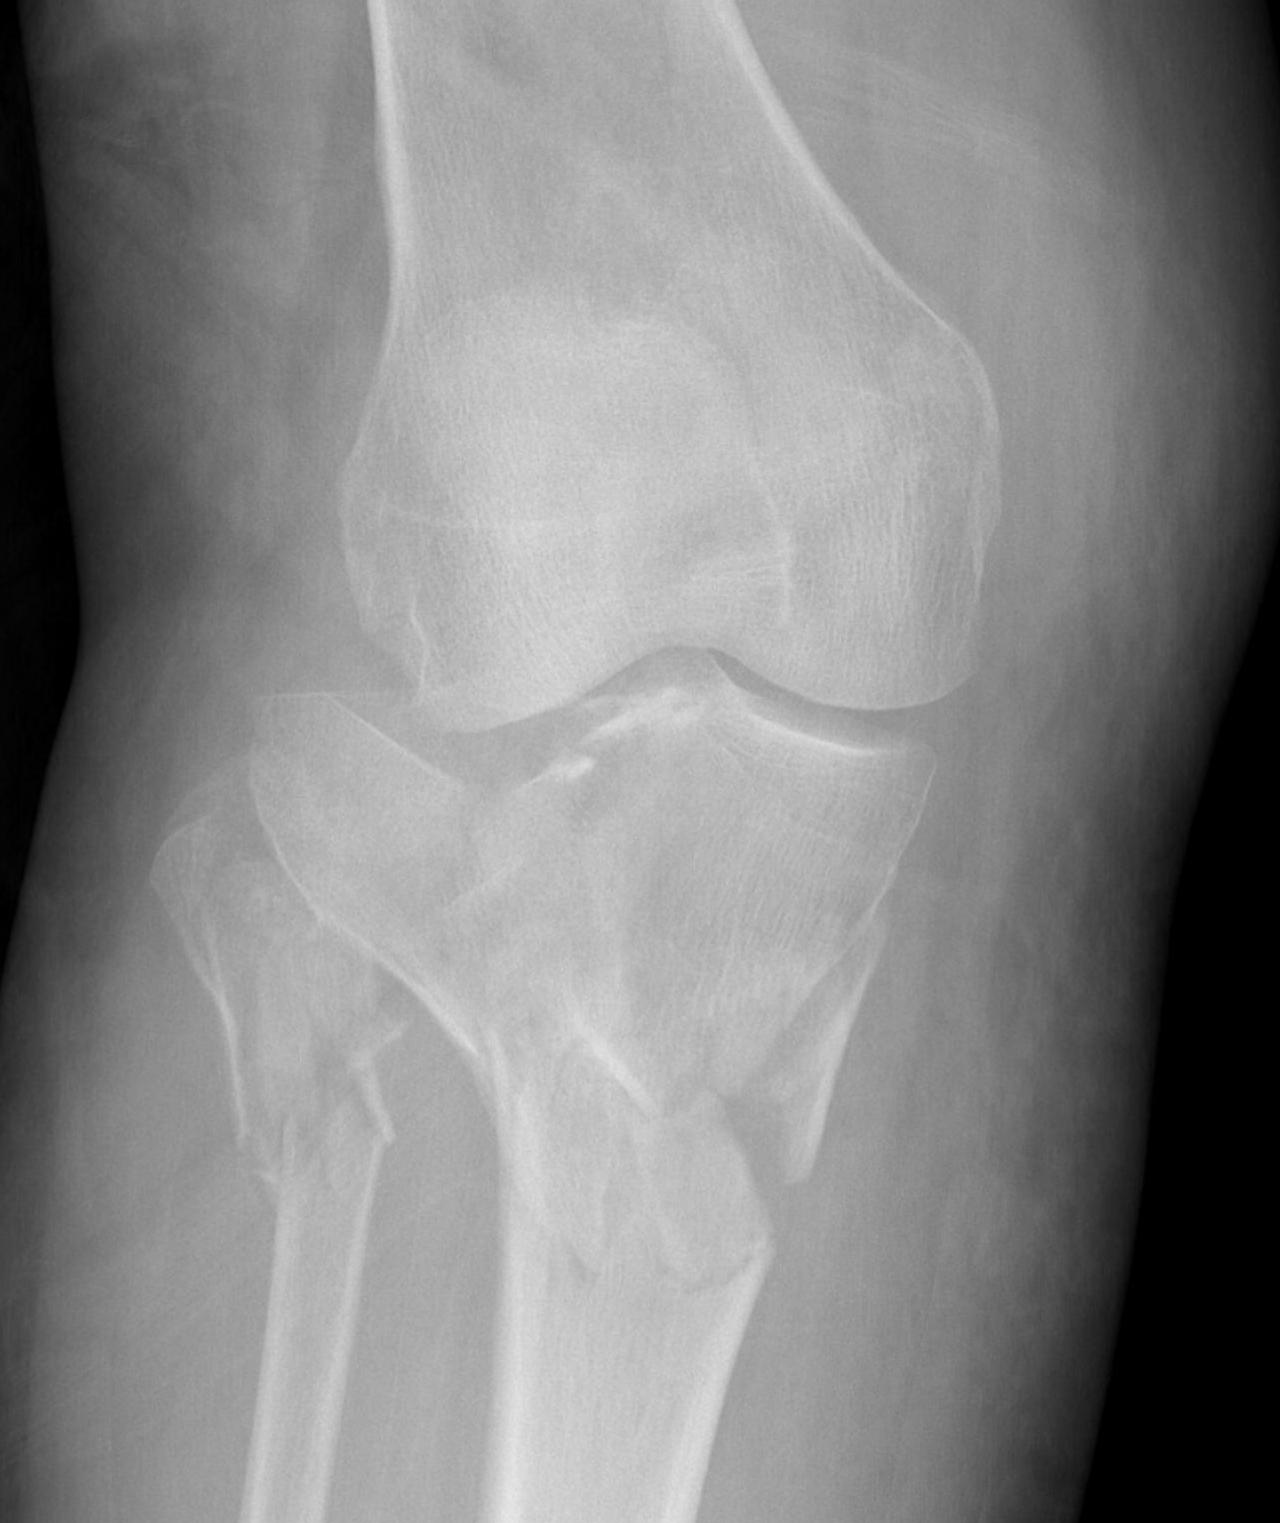

IV. Medial plateau & intercondylar eminence

- high velocity injury associated with ACL / LCL / CPN injury

- can be low injury / osteoporotic and often unreconstructable